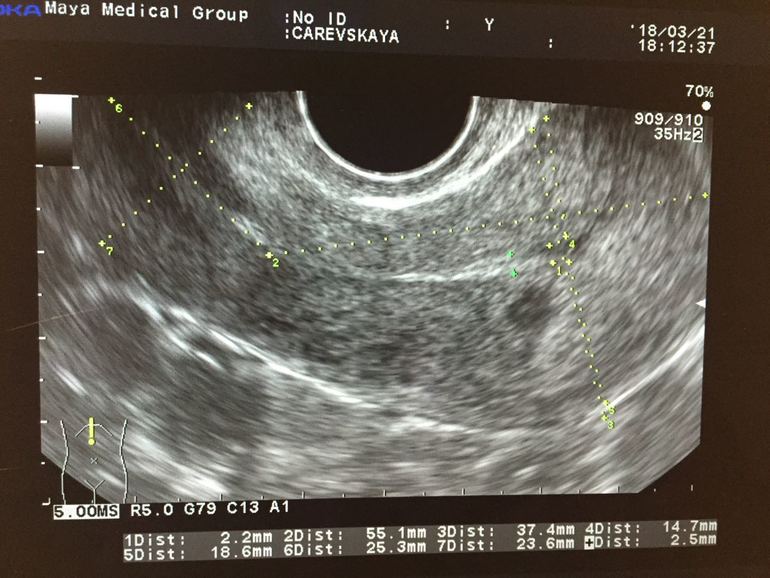

Всем привет! Давно ничего не писала после выкидышей) у меня вот что: на фоне приема ОК произошел горональный сбой. М пришли раньше. Потом произошла О, но эндик благодаря ОК был тонким, чем надо. И вот на узи нашли в средней трети марки Анэхогенное образование без видимо капсулы. М были 1 ого Марта.

Девочки, у кого было такое? В инете вплоть до рака инфу нашла (((( фото прикрепила.